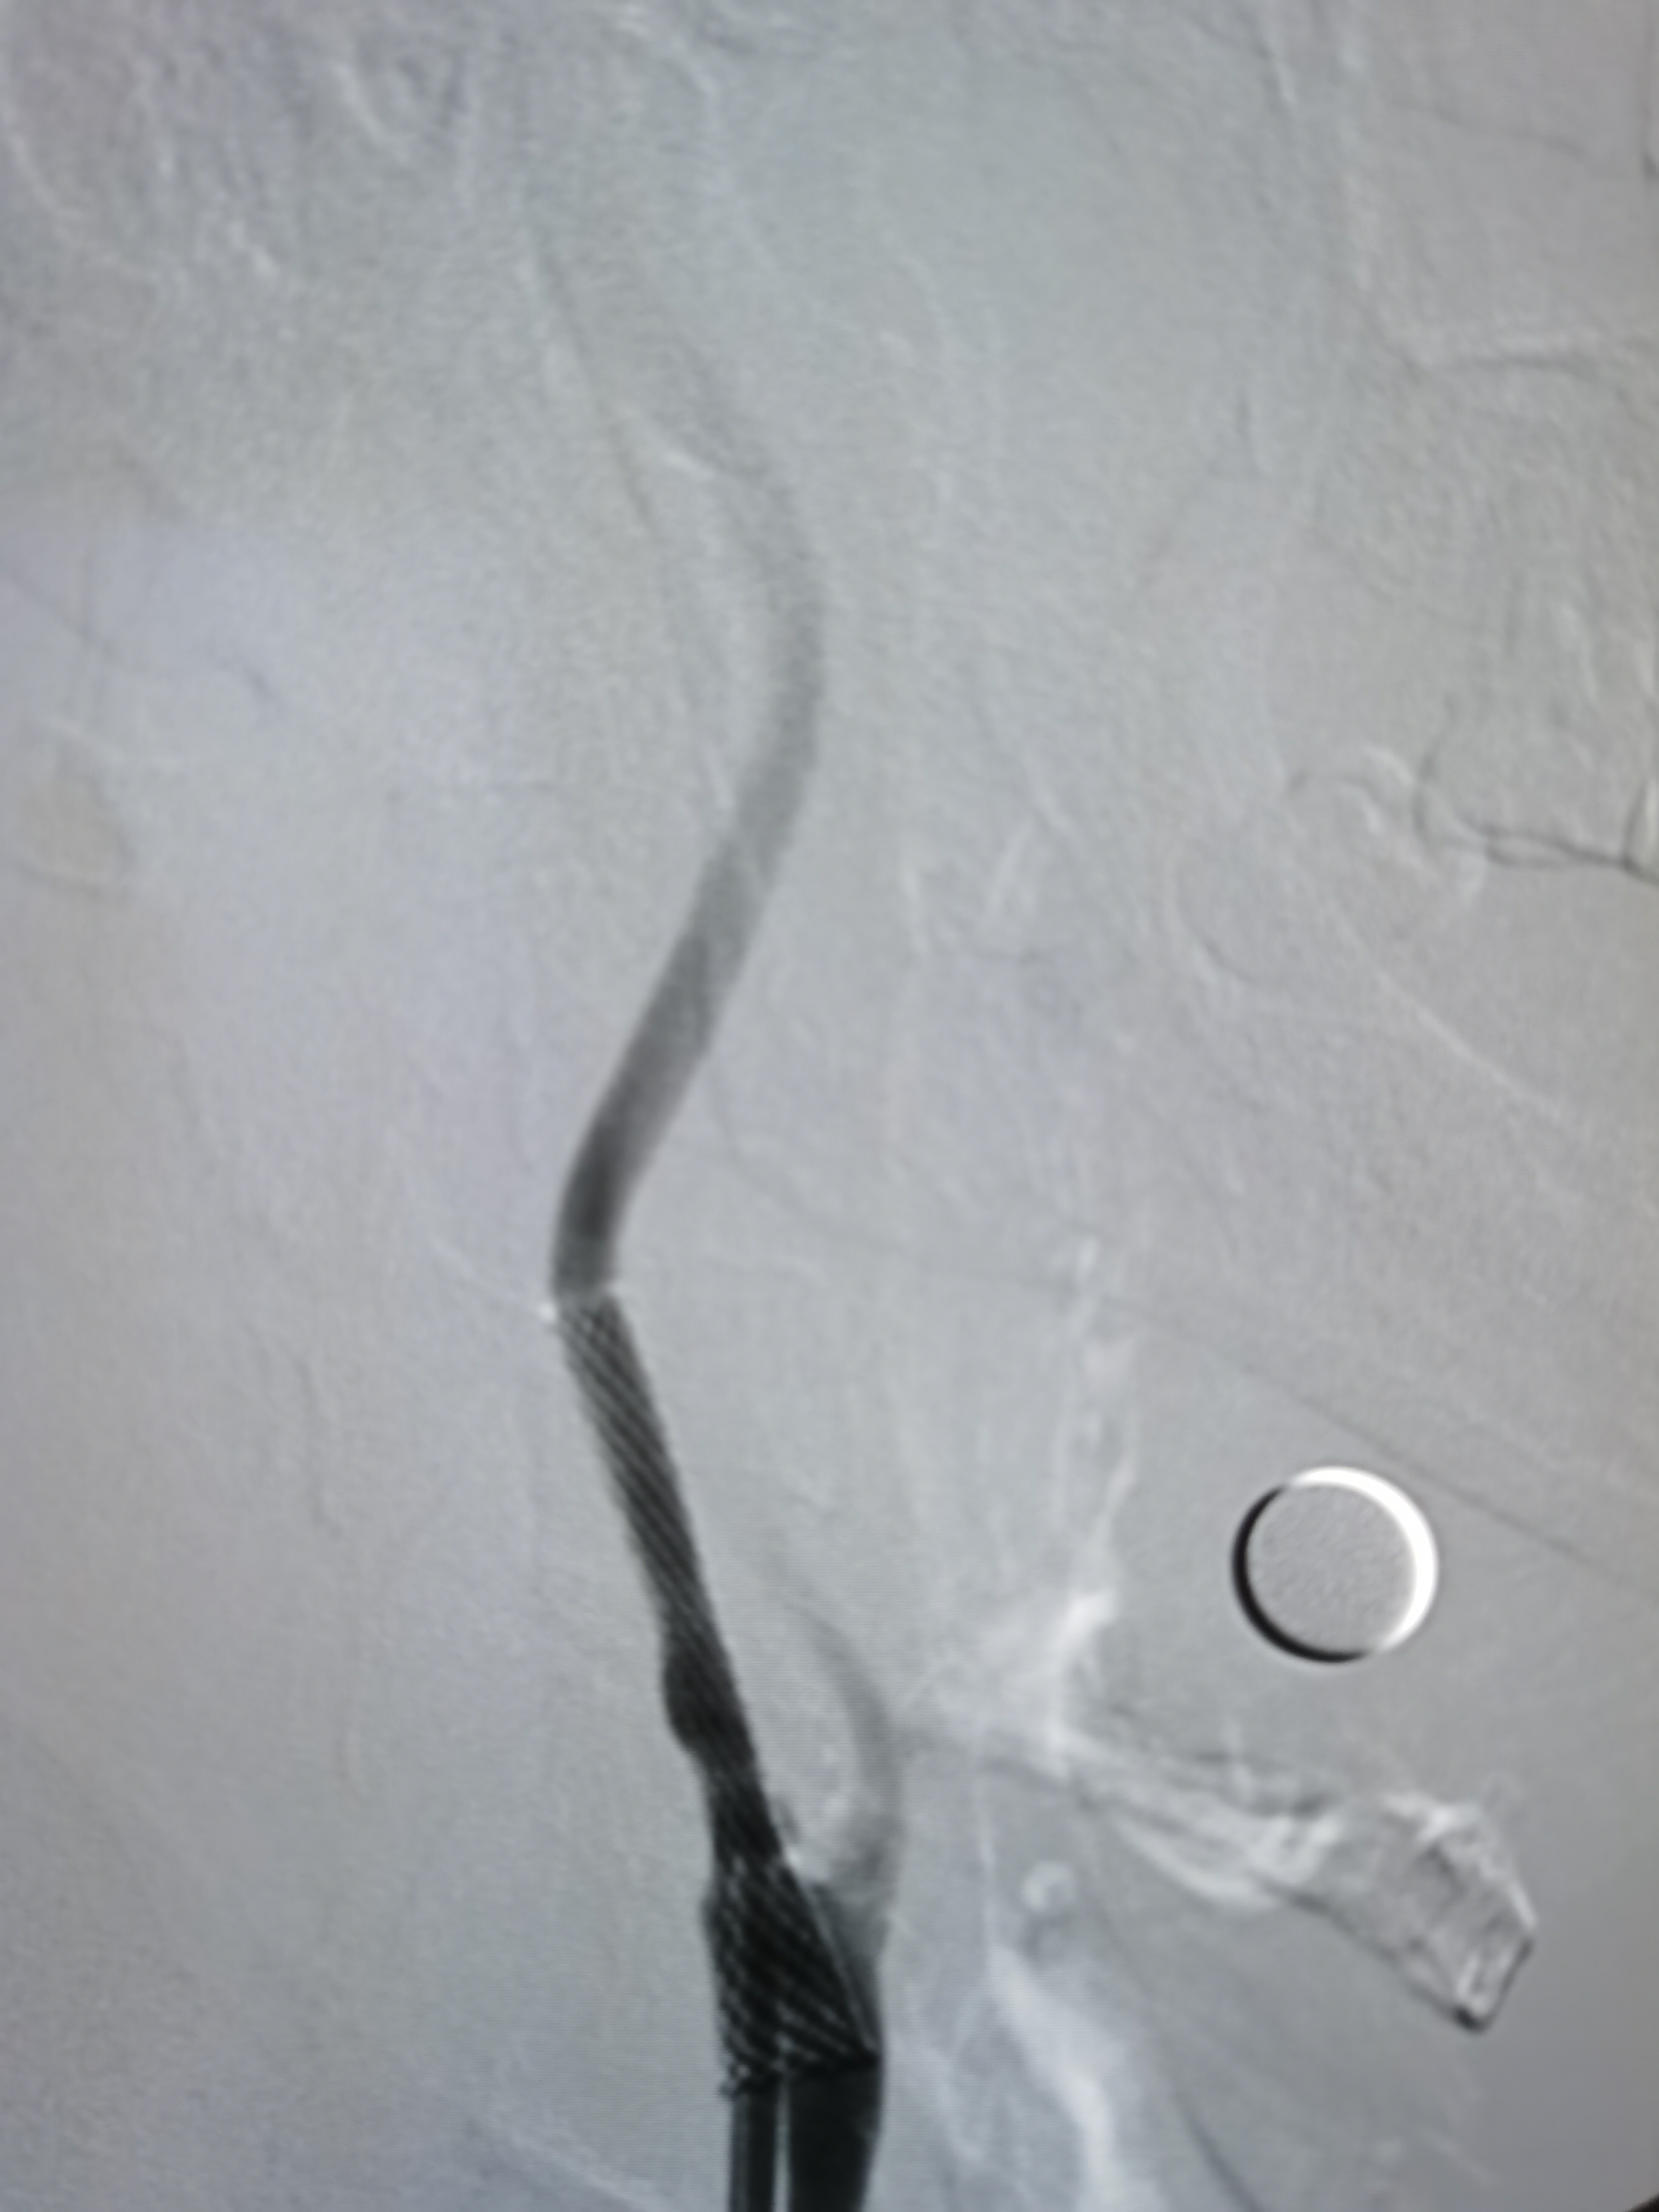

8F导引导管到位右侧颈总动脉末端,明确狭窄。

微导丝顺利通过病变,交换入远端保护伞。